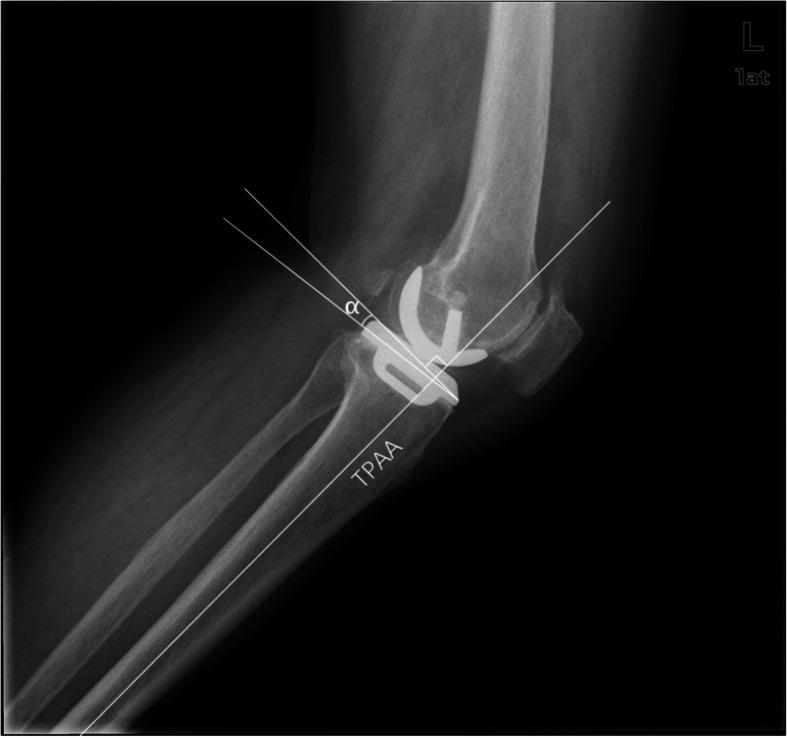

To evaluate the effect of medial posterior tibial slope (PTS) on mid-term postoperative range of motion (ROM) and functional improvement of the knee after medial unicompartmental knee arthroplasty (UKA).

Medical records of 113 patients who had undergone 124 medial UKAs between April 2009 through April 2014 were reviewed retrospectively. The mean follow-up lasted 7.6 years (range, 6.2-11.2 years). Collected were demographic data, including gender, age, height, weight of the patients. Anteroposterior (AP) and lateral knee radiographs of the operated knees were available in all patients. The knee function was evaluated during office follow-up or hospital stay. Meanwhile, postoperative PTS, ROM, maximal knee flexion and Hospital for Special Surgery (HSS) knee score (pre-/postoperative) of the operated side were measured and assessed. According to the size of the PTS, patients were divided into 3 groups: group 1 (<4°), group 2 (4° ~ 7°) and group 3 (>7°). The association between PTS and the knee function was investigated.

In our cohort, the average PTS was 2.7° ± 0.6° in group 1, 5.6° ± 0.9° in group 2 and 8.7° ± 1.2° in group 3. Pairwise comparisons showed significant differences among them (p < 0.01). The average maximal flexion range of postoperative knees in each group was 112.4° ± 5.6°, 116.4° ± 7.2°, and 117.5° ± 6.1°, respectively, with significant difference found between group 1 and group 2 (p < 0.05), and between group 1 and group 3 (p < 0.05). However, the gender, age, and body mass index (BMI) did not differ between three groups and there was no significant difference between groups in terms of pre-/postoperative HSS scores or postoperative knee ROM.

A mid-term follow-up showed that an appropriate PTS (4° ~ 7°) can help improve the postoperative flexion of knee. On the other hand, too small a PTS could lead to limited postoperative knee flexion. Therefore, the PTS less than 4° should be avoided during medial UKA.